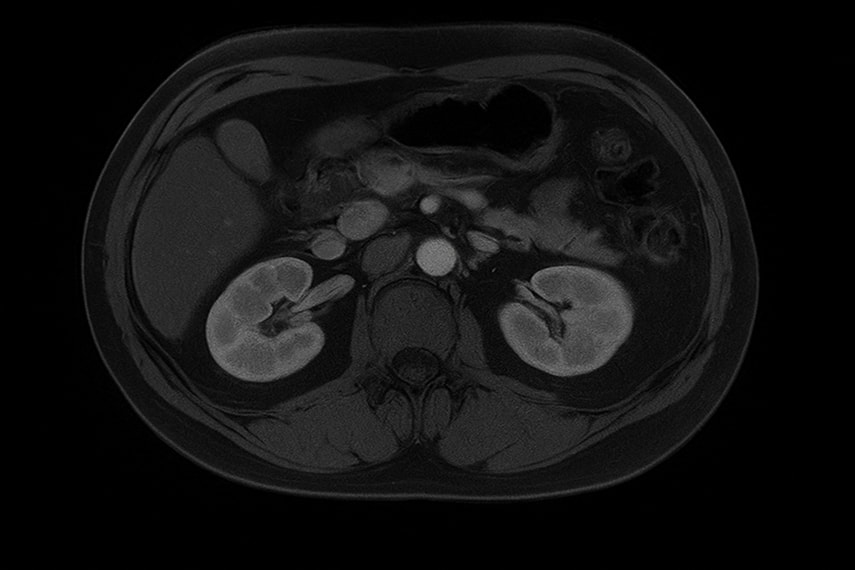

МРТ надпочечников — это неинвазивный метод, основанный на применении мощного магнитного поля и радиочастотных импульсов. Он позволяет получить максимально информативные послойные снимки, которые отражают размеры, форму, структуру и функцию надпочечников, а также состояние окружающих тканей брюшной полости.

Этот метод особенно ценен для дифференциации аденомы надпочечников и других патологий надпочечников на ранних стадиях. Новейшие протоколы химического сдвига повышают диагностическую точность. Именно они позволяют проводить диагностику и достоверно отличать доброкачественные образования от злокачественных новообразований и метастазов без ионизирующего излучения, что важно для молодых пациентов и беременных.

МРТ надпочечников в современной диагностической клинике проводится на высокопольных томографах (1,5–3 Тл) с применением торсовой катушки для максимальной детализации.

Пациент ложится на выдвижной стол, область сканирования — верхний отдел брюшной полости. Для повышения информативности, особенно при подозрении на злокачественные новообразования, может вводиться контрастное вещество на основе гадолиния.